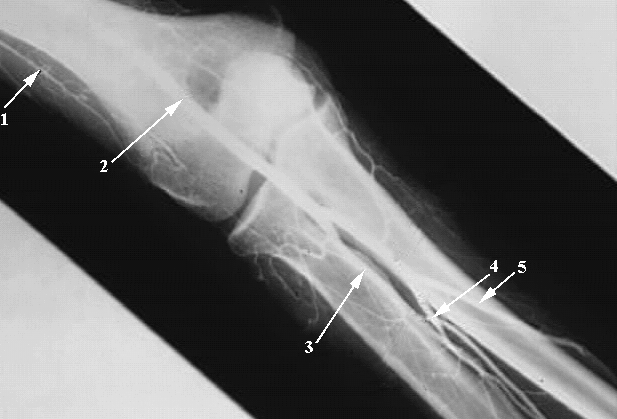

Upper Limbs: Elbow Collateral Vessels:

1. Radial Colleteral Artery

2. Brachial Artery

3. Radial Artery

4. Common Interosseous Artery

5. Ulnar Artery.